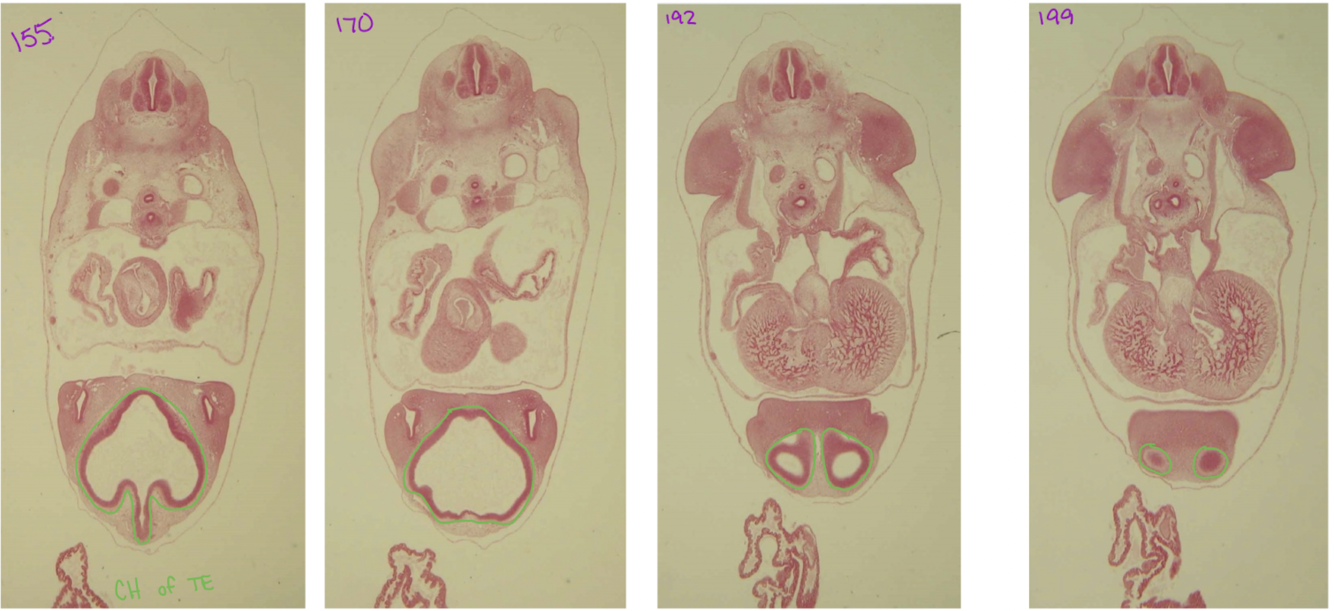

cerebral hemisphere

telencephalon becomes constricted into two “future cerebral hemisphere

diencephalon→ telencephalon → cerebral hemisphere

Telencephalon

diencephalon → telencephalon → cerebral hemisphere